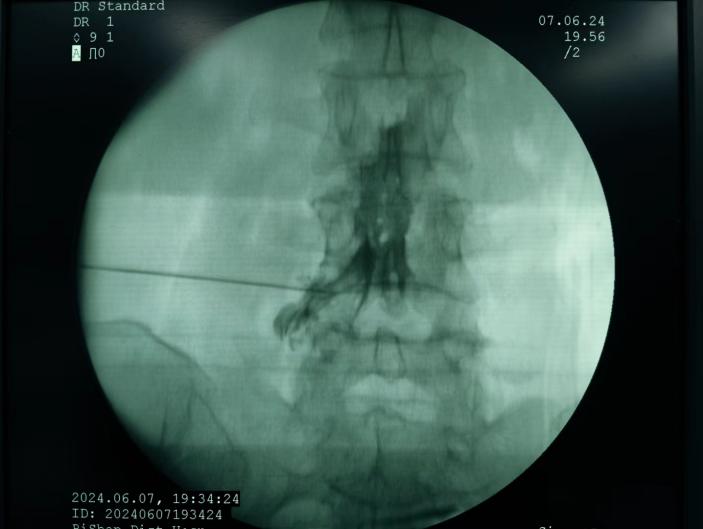

ac874aa18aee42e58f8890dd86cc1a27.Jpeg  09566eb81ad84804af008e90e5297638.Jpeg

椎間盤射頻消融術(shù)、膠原酶椎間盤化學(xué)消融術(shù)